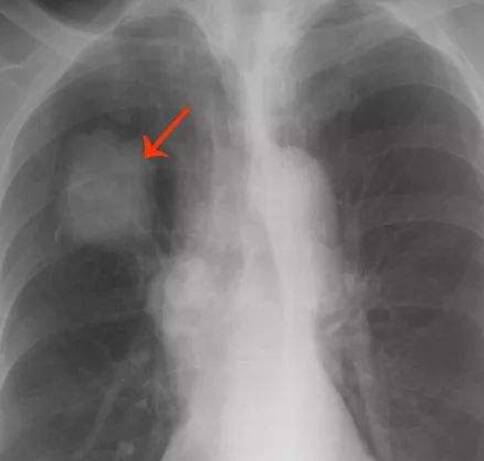

出國(guó)看?。悍伟┥飿?biāo)志物能提高風(fēng)險(xiǎn)預(yù)估